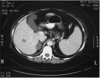

Adrenal Cortical Carcinoma

Adrenal Cortical Carcinoma

Adrenal Cortical Carcinoma

Adrenal Cortical Carcinoma